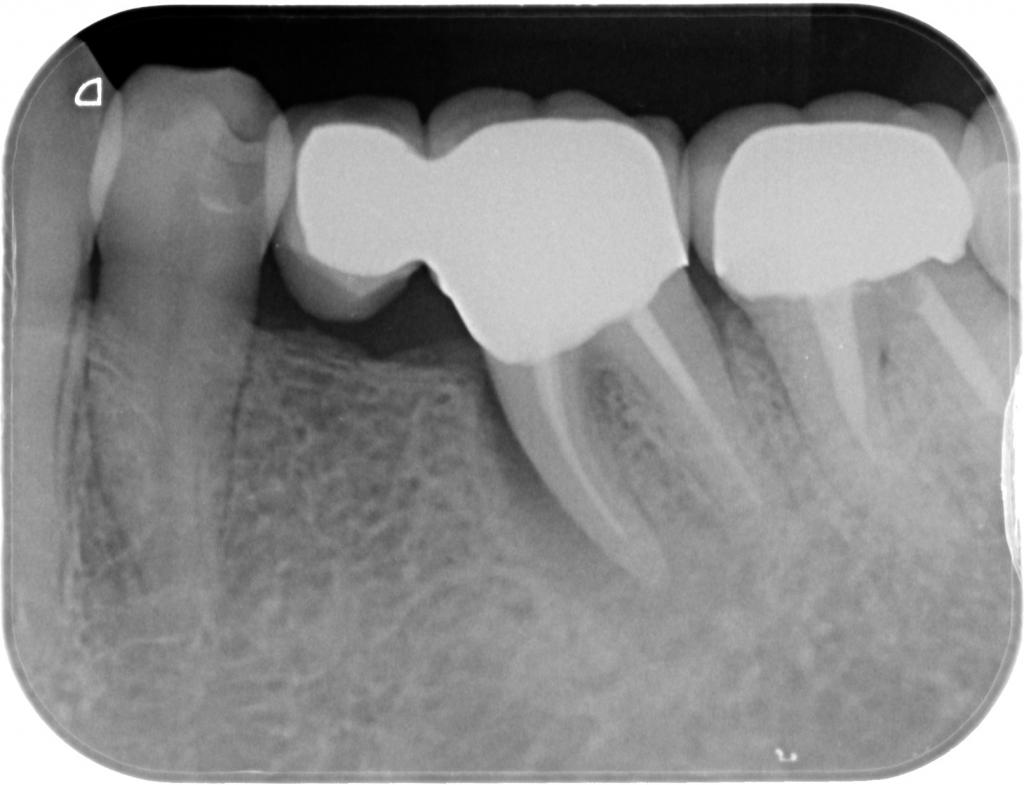

- その時のレントゲン写真です。

根っこの周囲が、上から下まで黒くなっています。

「歯根破折」した時の典型的な写真です。

患者さんと相談し、抜歯してインプラントにすることにしました。